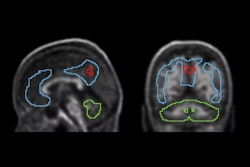

FDG, early perfusion amyloid-PET, and late standard amyloid-PET in a patient with Alzheimer’s disease (AD) ([F-18] Flutemetamol, panel A) and in a patient with behavioral variant of fronto-temporal dementia (bvFTD) ([F-18] Florbetaben, panel B). Regardless of the disease-related pattern (posterior in patient A and anterior in patient B), FDG and early perfusion imaging show largely overlapping distribution with small differences. Higher early-phase amyloid tracer distribution with respect to FDG uptake is expected in the brain stem, cerebellum, anterior cingulate, and thalamus, while lower uptake compared to FDG is present in the prefrontal, orbitofrontal, posterior parietal, and superior temporal regions.Prof. Silvia Morbelli et al and EANM Journal